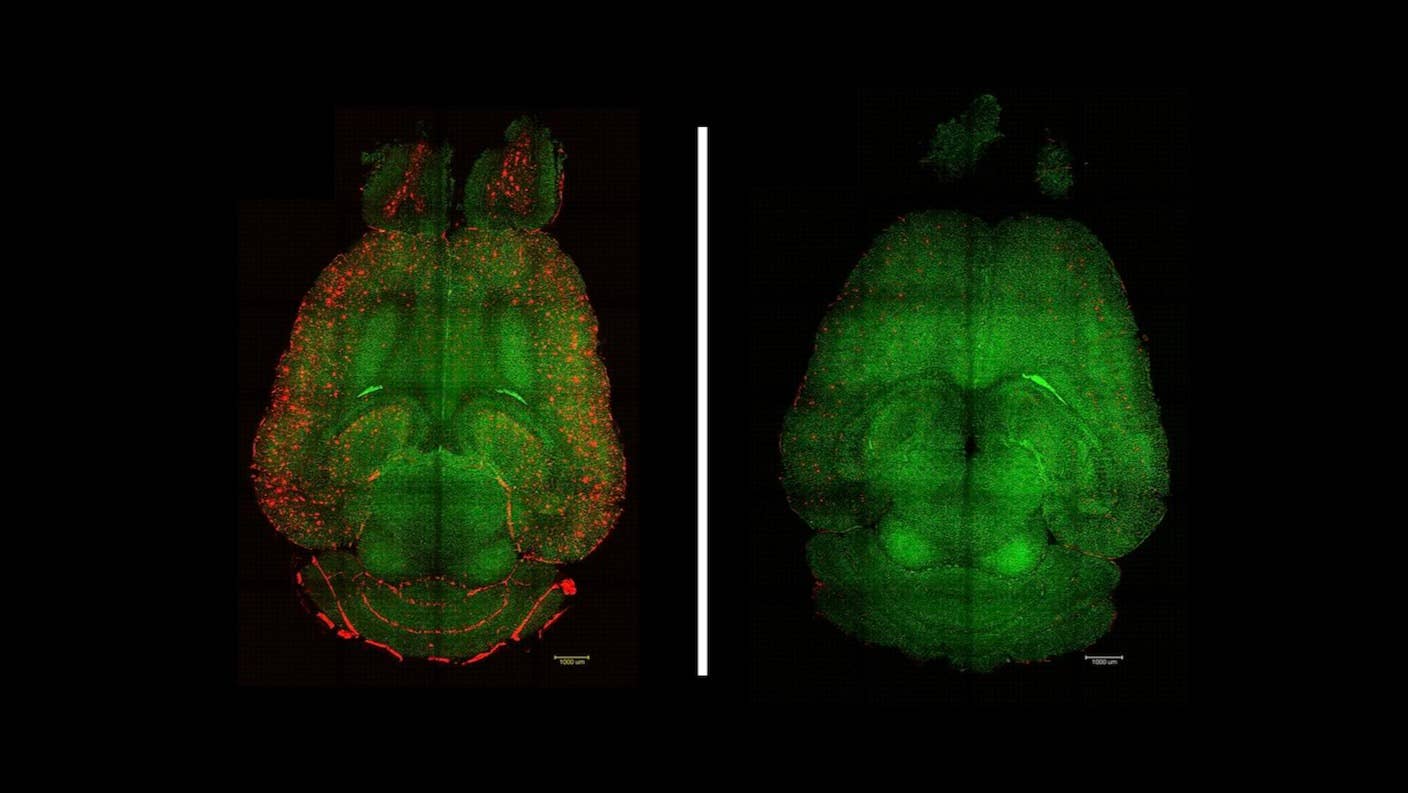

Plaques (red) cleared from vessels (green) in mice. Untreated brain (left) and treated brain (right) / Institute for Bioengineering of Catalonia (IBEC)

In mice modeling Alzheimer’s disease, three shots tricked the barrier into trafficking the toxic proteins out of the brain and into the bloodstream, where they were rapidly destroyed. In just an hour, the treatment slashed amyloid-beta levels in half. The mice also better remembered spaces—kind of like where you last parked your car—with effects lasting for six months.

The team gave mice modeling Alzheimer’s disease three injections of the nanoparticle—it slashed levels of amyloid-beta. “Only one hour after the injection we observed a reduction of 50-60 percent in Aβ [amyloid-beta] amount inside the brain,” said study author Junyang Chen.

Reactivating transcytosis—the process of shuttling proteins across the blood-brain barrier—was only partly responsible for the improvement. The treatment also restored the health of the barrier itself, rejuvenating its structure and adding more protein shuttles.